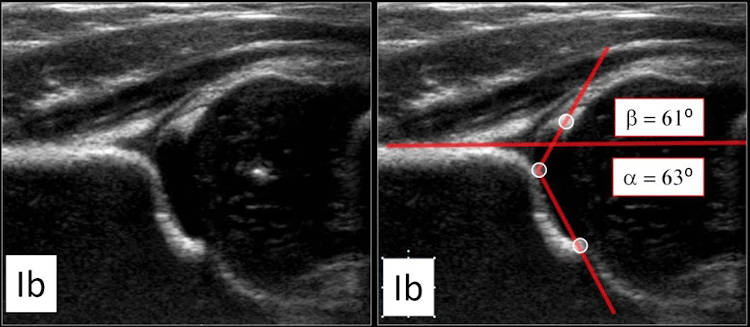

όπως και λογισμικό για έλεγχο δυσπλαστικού ισχίου στα νεογνά (μπορούμε να εξετάσουμε την επικέντρωση της μηριαίας κεφαλής στη κοτύλη, την λοξότητα της κοτύλης και την σταθερότητα της αρθρώσης με τον δυναμικό υπέρηχο σε ειδικό κρεβατάκι)